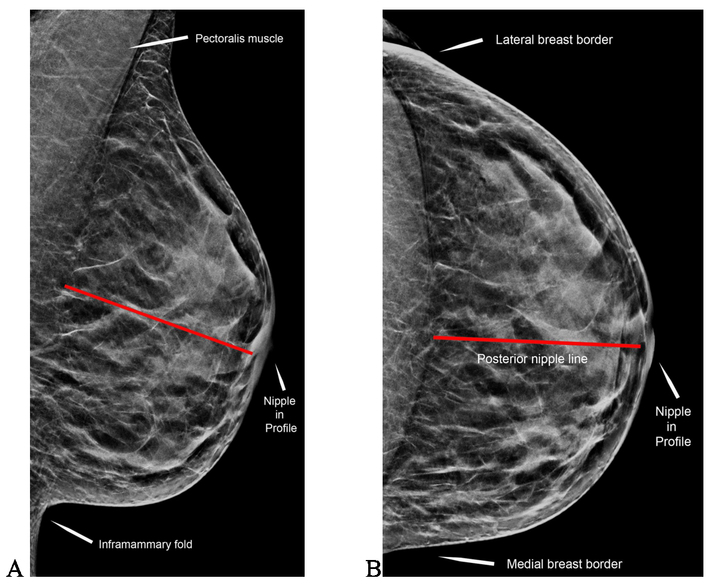

The pectoralis muscle should extend to at least within ________ cm of the posterior nipple line

1 cm

Using ACR accrediation criteria for clinical image evaluation, what is recommended for visualization of the pectoralis muscle on mammorgraphy?

extends to the level of the posterior nipple line

nipple is required to be in profile on how many views?

at least one view